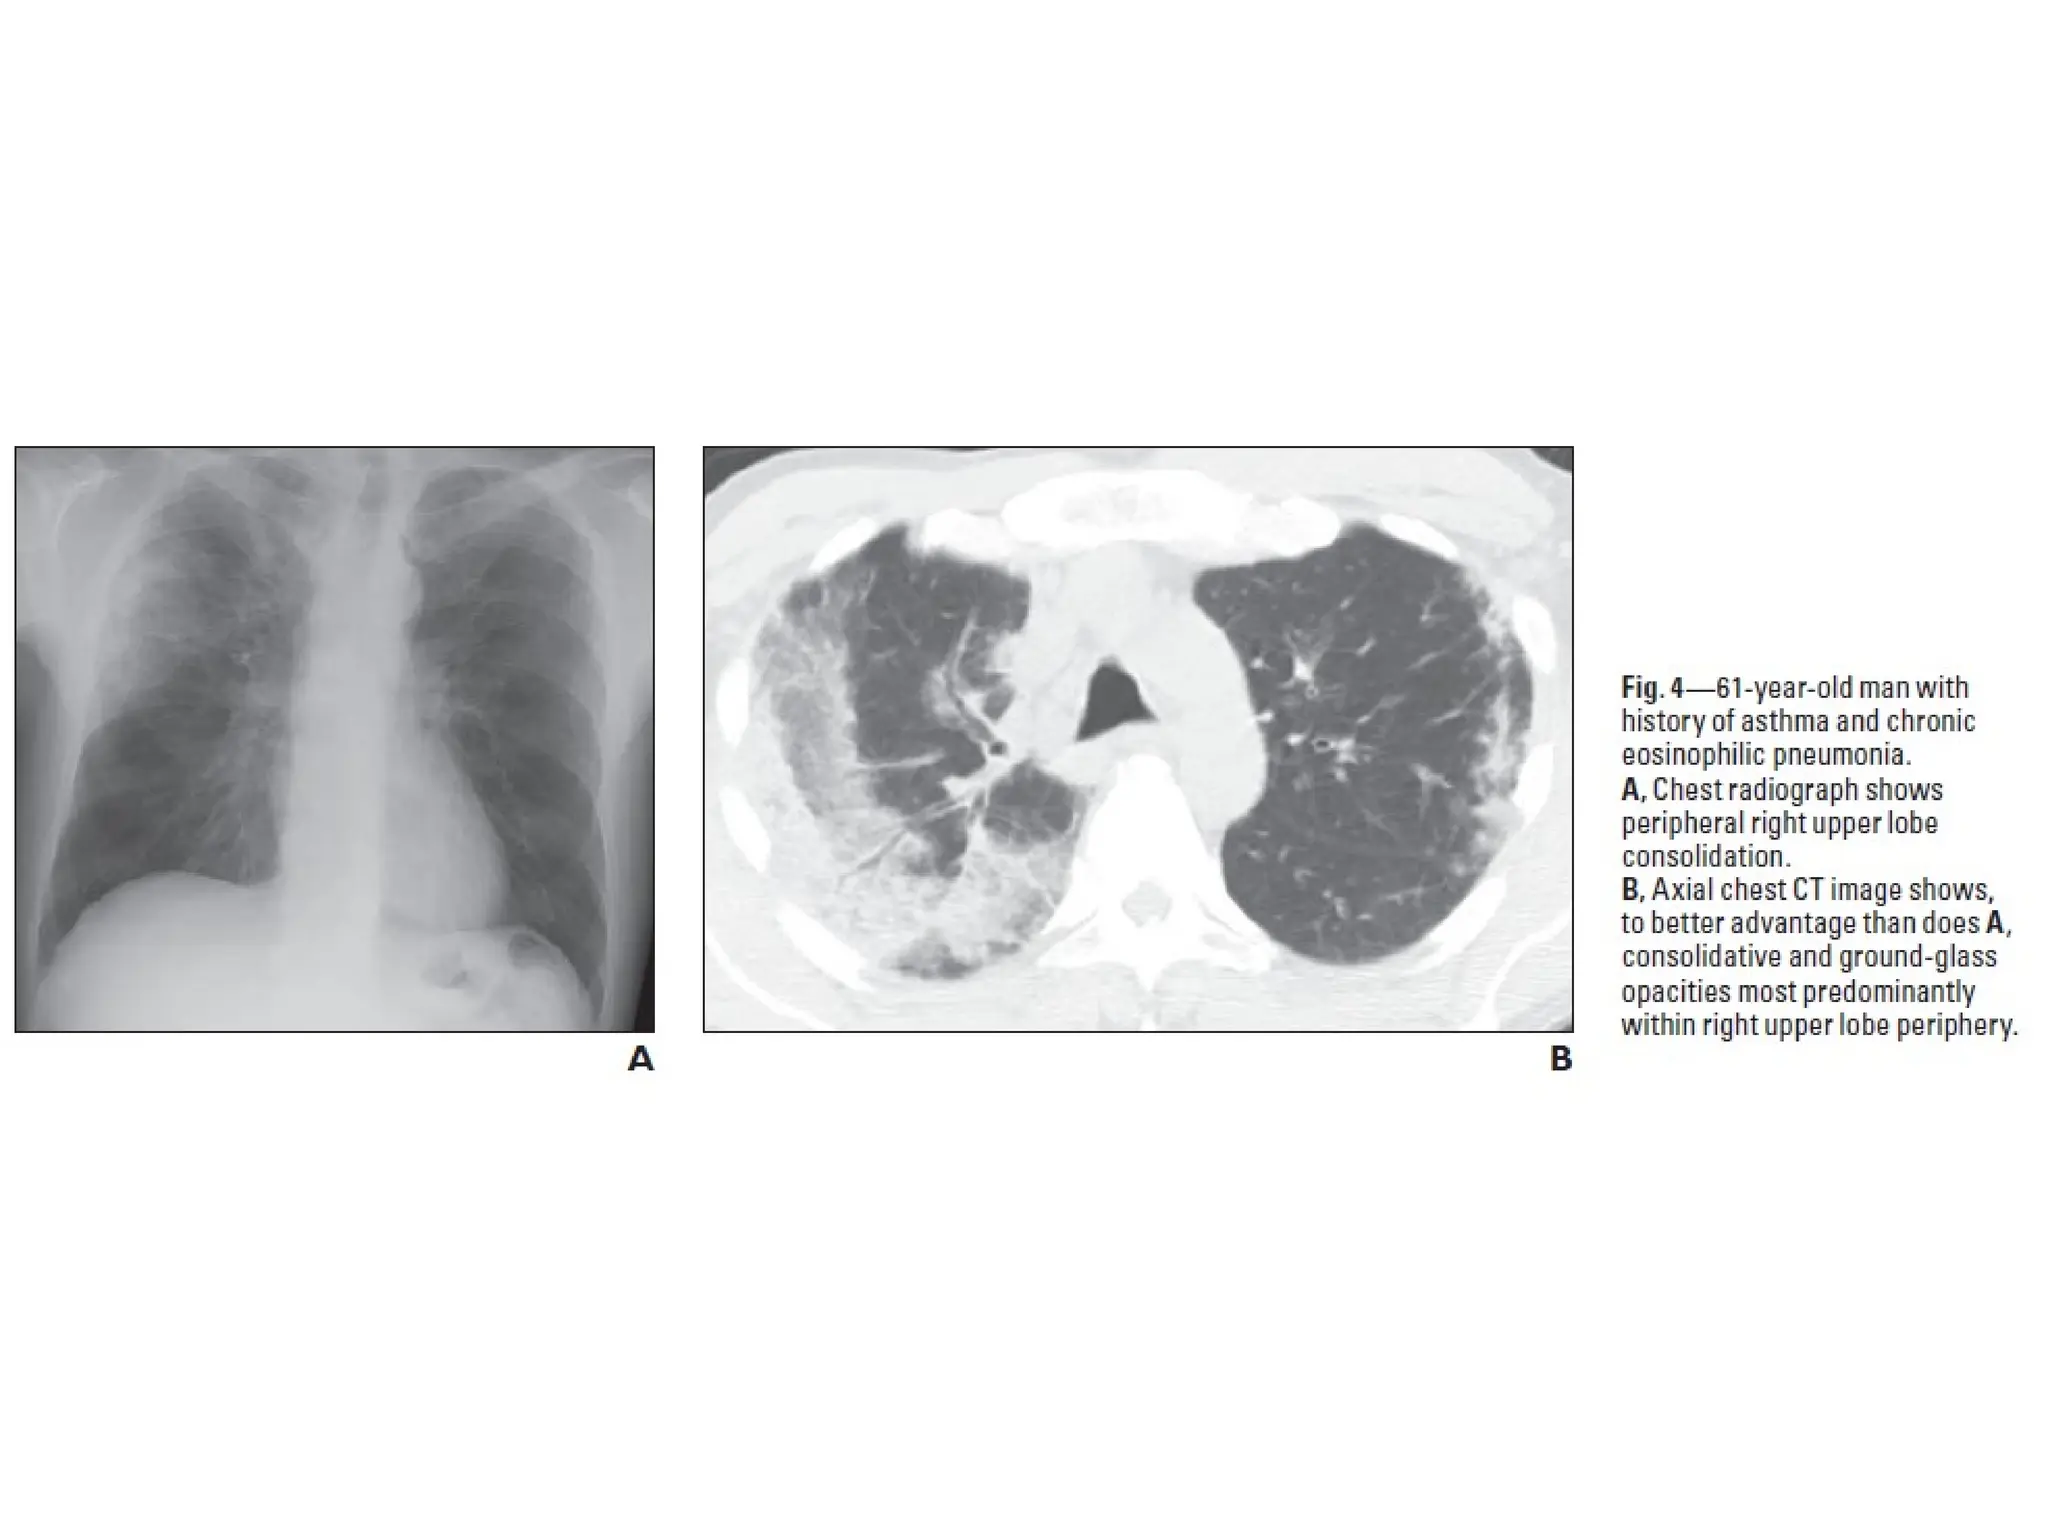

• Chronic eosinophilic pneumonia

• Chronic eosinophilic pneumonia is an idiopathic

condition characterized by filling of the alveoli with

eosinophils.

• Often affects patients with a history of atopy, asthma

and allergic rhinitis.

• Symptoms usually present for >1 month and include cough,

high fever, night sweats, dyspnea, malaise, and marked

weight loss

• Blood eosinophilia present in 90% of patients and sputum

eosinophilia in 50%.

• Imaging Findings

• Ground glass and consolidation in a peripheral and

upper lobe distribution (photographic negative of

central pulmonary edema)

• Not usually migratory (differentiates from organising

pneumonia)

• Responds dramatically to steroid treatment.

• After treatment residual fibrosis seen in some patients